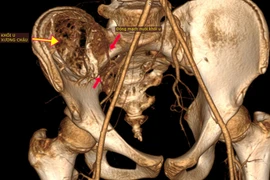

(khoahocdoisong.vn) - Chỉ nghĩ con bị đau xương tuổi dậy thì nào ngờ trẻ 12 tuổi bị u máu khổng lồ phá hủy nửa cánh xương chậu và đe dọa tính mạng. Nhờ kỹ thuật nút mạch và ghép xương, các bác sĩ tại hai bệnh viện kết hợp đã loại bỏ thành công khối u máu và trám xương thành công cho trẻ.